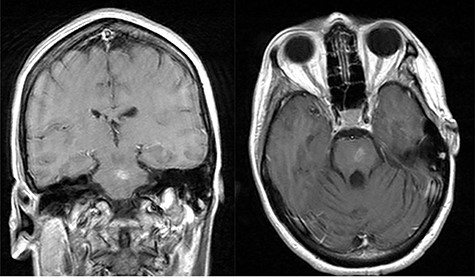

She presented to clinic for follow-up evaluation 11 weeks after discharge. Overall, she is doing very well and ambulating independently with a cane. On physical exam, CNII-XII are intact. She has no bulbar deficits. She has 4/5 strength in all major muscle groups on the right side. Repeat MRI has shown near resolution of the abscess (Fig. 3a and b).

Post-op axial and coronal MRIs, 11 weeks following discharge, demonstrating resolution of the pontine abscess with small area of residual scarring; source: http://pacsweb.wjmc.org.